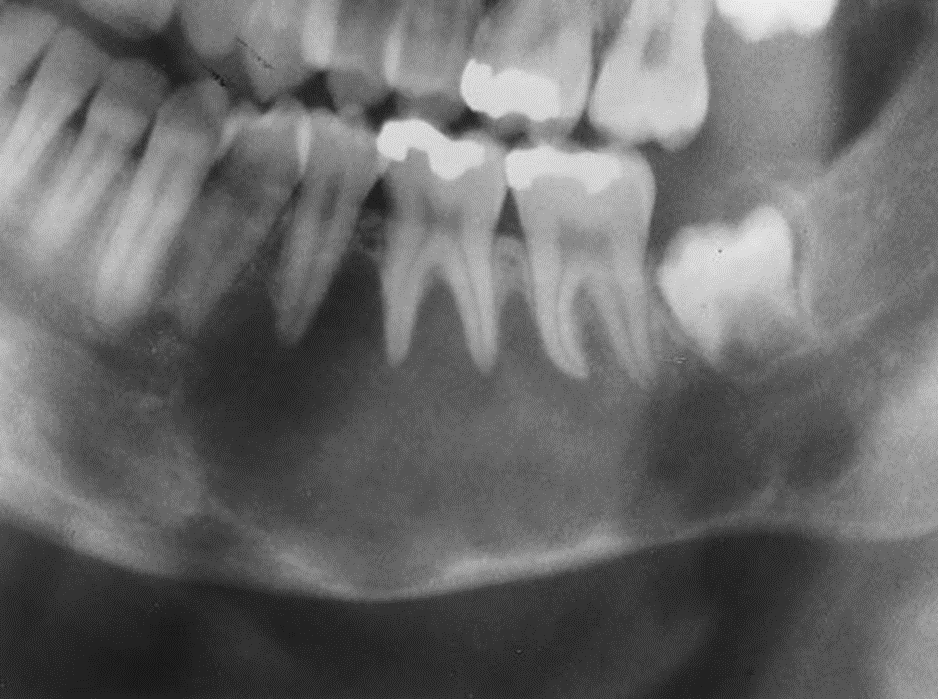

4. This 72-year-old woman presented with loose 20-yearold dentures and slight intermittent pain under the lower denture. She stated she had her teeth extracted because of severe untreated caries and abscessed teeth. The radiolucent lesion was detected on a radiograph of the painful area.

What is your diagnostic impression?